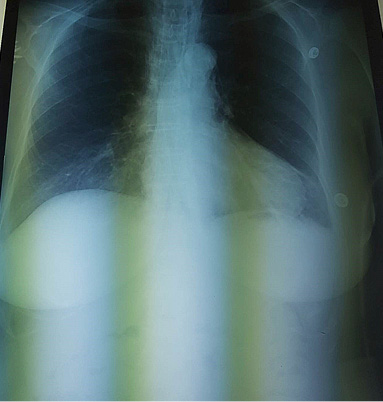

A cranial and thoracic computed tomography (CT) showed diffuse soft tissues emphysema from the thoracic region to the neck and face (Figure 2), and mediastinal emphysema in all compartments (Figure 3), and interruption of tracheal continuity 4 cm cranial from the bifurcation (Figure 4).

Figure 2. Diffuse soft tissues emphysema